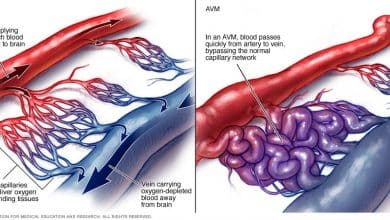

مرض AVM تشوه الشرايين الوعائية

AVM ( تشوه الشرايين الوعائية ) – هو عبارة عن كتلة وعائية في الدماغ ، وهو اتصال الشريان بالأوردة. قد تكبر مع مرور الوقت. كلما زاد حجم الـ arteriovenous malform